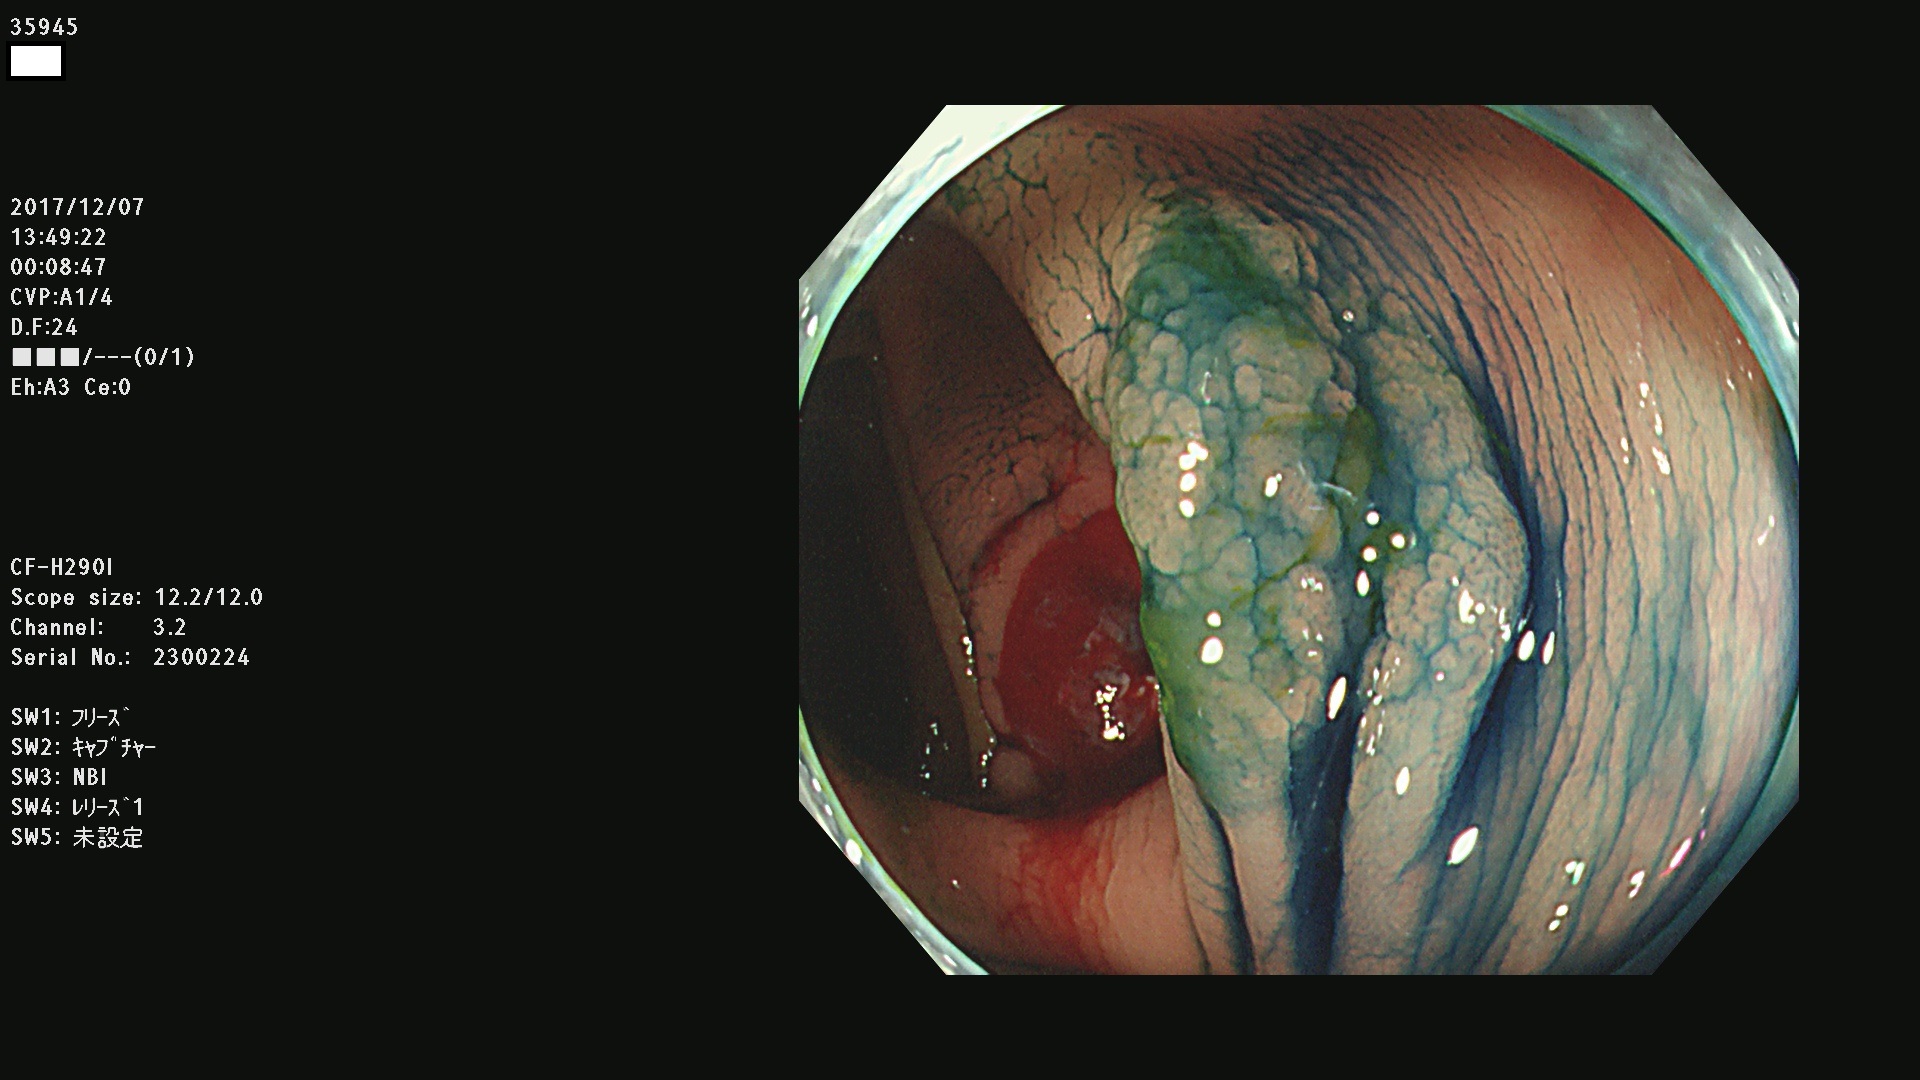

腺腫発見率43 % (カルテ番号 35900〜35999の100名の方の検査結果で集計)大腸癌検診最新情報

以下のカルテ番号の方に腺腫(Adenoma,Group3〜5)が見つかりました(集計法)

35900 35901 35904 35908 35912(SSA/Pのみ) 35914 35918 35922 35925 35926 35928 35931 35932 35933 35934 35937 35939 35943 35945 35947 35949 35951(SSA/Pのみ) 35952 35958 35959 35963 35964(SSA/Pのみ) 35965 35970 35972 35976(SSA/Pのみ) 35977 35978 35979(SSA/Pのみ) 35980(SSA/Pのみ) 35982 35983 35985 35991 35993 35995 35997 35999

発見困難で危険性の高い平坦型病変(上記100名より抽出) ![]()